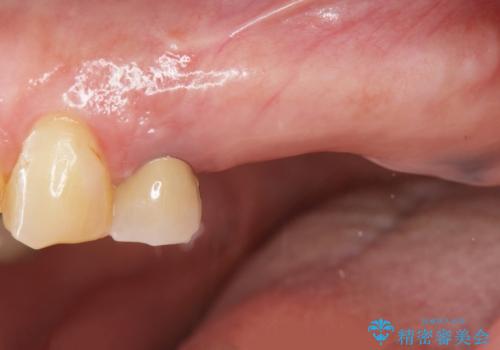

- 奥歯を虫歯で失ってしまい、しっかりと噛めるようになりたい、と希望され来院されました。

3本の歯(クラウン)を2本のインプラントで支えるインプラントブリッジによる咬合機能の回復を計画します。